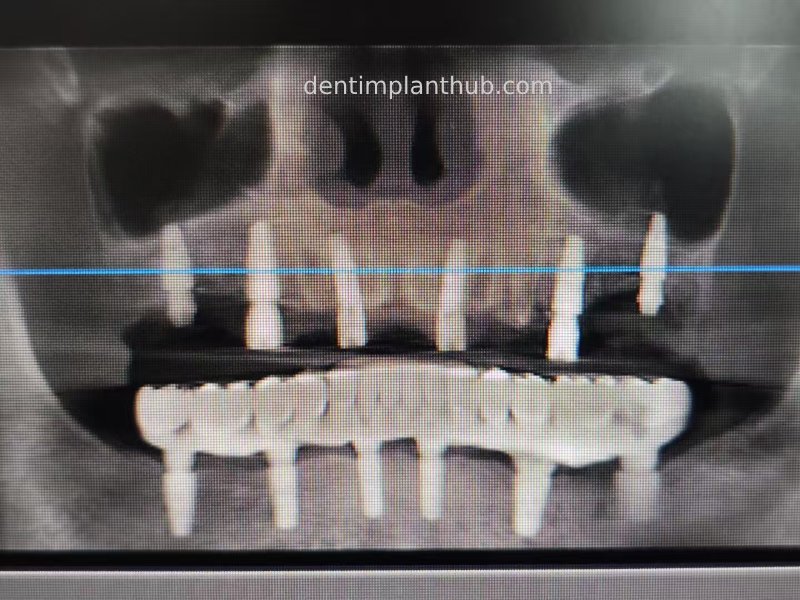

Case 5: 11 implants in one surgical implant procedure